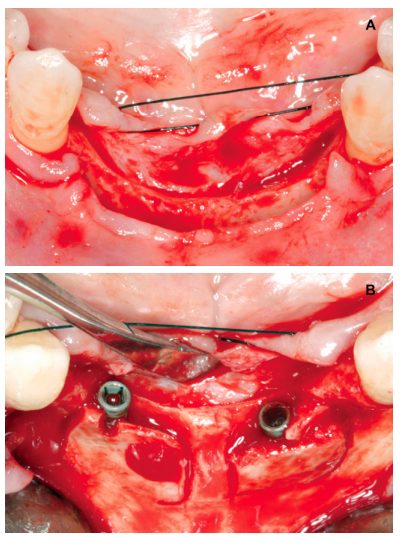

Aft er 4 years, the second and third quadrant molars began to have excessive mobility and serious periodontal problems, so it was decided to remove them and regenerate the alveoli with PRGF-Endoret. Once the area was regenerated (a month and a half later), a conebeam was performed to evaluate the residual bone volume. It can be seen how there was an uneven bone crest with areas of 3.3 mm in height up to a maximum of 7 mm (Figures 9 and 10). On this occasion, due to the protocol change described above, we opted for the direct insertion of extra-short implants, since the surgical protocols to address this type of situation in 2011 varied substantially, with these implants being a first-line tool for the treatment of this type of atrophy (Figure 11). Two extra-short implants were selected (5.5 mm diameter x 6.5 mm length for tooth 26, and 6 mm diameter x 5.5 mm length for tooth 27).